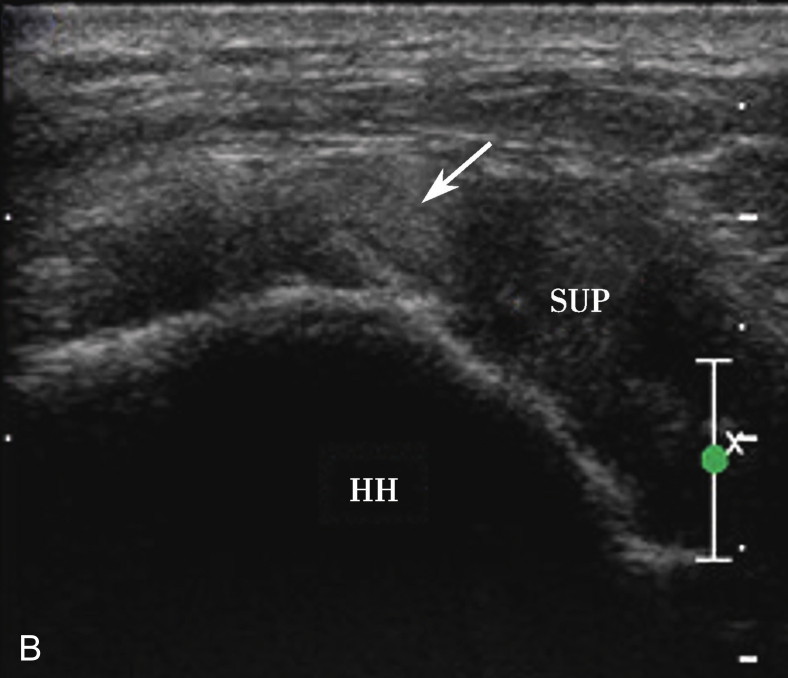

2.当针尖进入滑囊后(图2-1-5),可推注少量药物,若推注顺利可观察到滑囊扩张及药物的弥散(图2-1-6),同时也表明针尖准确位于滑囊内,可继续推注混合药物3~5ml。若推注受阻,原因有可能是针尖在滑囊组织内,需重新调整针尖,也可能是滑囊内粘连明显所致,可加大力度,利用液体推注的压力松解粘连,松解后可见粘连带呈线状稍强回声(图2-1-7),也可在粘连远端重新选择部位注入药物,这类患者可能需要多次治疗才能达到较好的疗效。

3.当肩袖回声不均匀,有可疑的滑囊面撕裂或全层撕裂,行超声引导下肩峰下-三角肌下滑囊造影检查,可提高对肩袖撕裂的诊断率。方法:将2~5ml生理盐水与0.5ml的超声造影剂混合后,注入肩峰下-三角肌下滑囊,无撕裂的滑囊呈线状高增强(图2-1-8),肩袖滑囊面部分撕裂可见造影剂混合液从滑囊进入肩袖肌腱内而未达肱骨头表面(图2-1-9),若观察到其进入肩关节腔或肱二头肌长头腱鞘,则诊断肩袖全层撕裂(图2-1-10)。

▲ 图2-1-9 超声引导下肩峰下-三角肌下滑囊造影图(二)

A.超声引导下滑囊内注入超声造影剂后,滑囊呈线状高增强,肌腱内可见局限性高增强,提示肌腱滑囊面部分撕裂(箭头);B.二维超声显示冈上肌腱(SUP)回声不均匀(箭头),但未见明显撕裂,HH:肱骨头